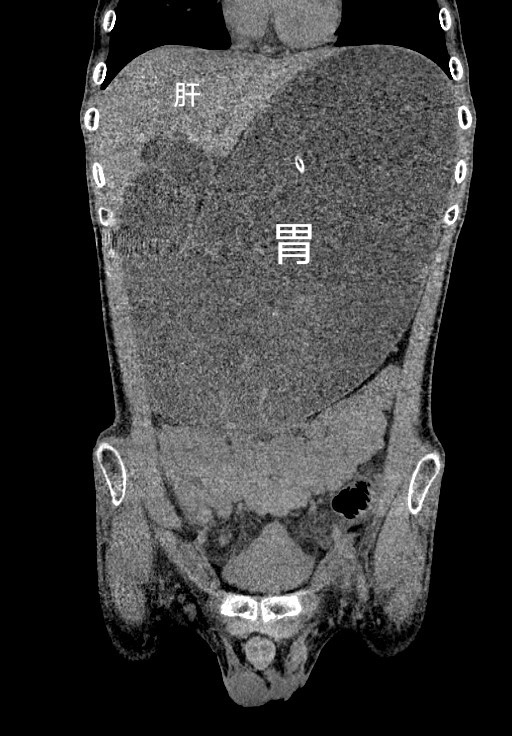

北京医院办理住院:18311458123

2、到达医院后,建议提前了解中国人民解放军第306医院的具体位置,一般而言,医院位于北京市海淀区北四环西路28号若需前往其原306医院就诊的全程安排他科室或进行特定检查,请提前与医院联系,以便顺利安排在前往医院的途中,可以留意沿途的地标建筑或公交站名,如安贞桥安贞医院等,以帮助确认行进方向同时,由于北京市内交通状况;战略支援部队特色医学中心原解放军第306医院医疗服务好1医疗设备先进医院拥有一批先进的医疗设备,如高精度CT核磁共振PETCT等,可以为患者提供更加精准的诊断和治疗2专家团队强大医院拥有一支由国内外知名的专家组成的医疗团队,包括多名博士硕士以及各类高级职称的专业医生,他们在多个;中国医疗看病难挂号难的问题,不能通过在挂号大厅里玩猫鼠游戏来治标,而是要通过在医保制度医生资质评审制度医疗资源分配制度等一系列上的问题来治本如果患者的委屈与痛哭,只是换来了常见的一阵风式的大检查,那么只能说原306医院就诊的全程安排我们的管理部门缺少正视问题的勇气与改革的决心306医院可以网上预约挂号;北京306医院现更名为中国人民解放军总医院第一医学中心,作为一家正规的综合性医院,具备完善的医疗设施专业的医疗团队和优质的服务态度根据相关政策规定,所有北京正规医院都被纳入医保定点医院范围,因此北京306医院自然也是医保定点医院三医保政策说明 本地就医北京市民在北京306医院就诊时。